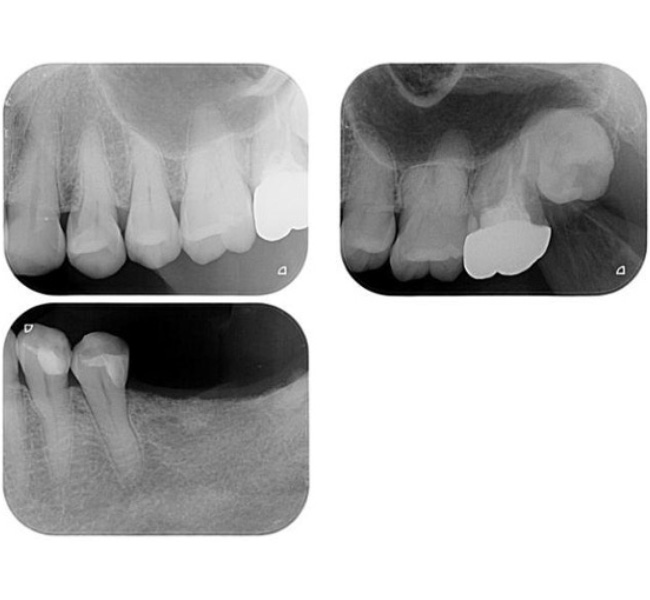

【口腔内写真】下顎咬合面

(噛み合わせの面)の全景

お口の内側(舌側)に見えるボコボコとした突起は「骨隆起」と呼ばれるもので、過酷な噛む力に耐えようとして身体が地盤を厚く補強した、いわば『力のストレス』の顕著な証拠です。

左下奥歯には、破折した根を分割した上で、強固なジルコニアクラウンを装着しています。繰り返された噛み合わせ調整の跡は、いかにこの部位に複雑で強い力が集中していたかを物語っています。

一方の右下奥歯は、激しい摩擦(咬耗)によって歯の表面のエナメル質が消失し、内部の象牙質が広範囲に露出しています。そこにある古い詰め物の周囲には、過度な力による「ヒビ(クラック)」を入り口として、細菌による二次的な虫歯が進行しています。

その他、各所に見られる段差のある不適合な修復物は、細菌の温床となりやすく、お口全体の健康を脅かす構造的なリスクとなっていました。

【口腔内写真】上顎咬合面

(上あごの噛み合わせ)の全景

上あごにおいても、歯を支える骨の幅が異常に大きく発達(骨隆起)しています。これは想定を超えた破壊的な荷重(オーバーロード)から歯を守ろうと、身体が必死に地盤を補強した痕跡です。

右上奥歯(6・7番)は、エナメル質が激しくすり減り、内部の象牙質が広範囲に露出しています。歯と歯の継ぎ目には荷重による「ヒビ(クラック)」が入り、そこから細菌の二次侵入を許しています。このまま放置すれば、いずれ歯が真っ二つに割れてしまう寸前の状態でした。

左上奥歯も同様に、重機で削り取ったかのような激しいすり減りが認められます。金属の被せ物には、繰り返された噛み合わせ調整の跡が深く刻まれており、いかに特定の部位に凄まじい力が集中していたかを物語っています。

お口全体の各所に見られる「ヒビに伴う虫歯」は、単なる磨き残しではなく、過度な力による構造破壊が引き金となって細菌の侵入を招いたものであり、根本的な「力のコントロール」が不可欠であることを示しています。